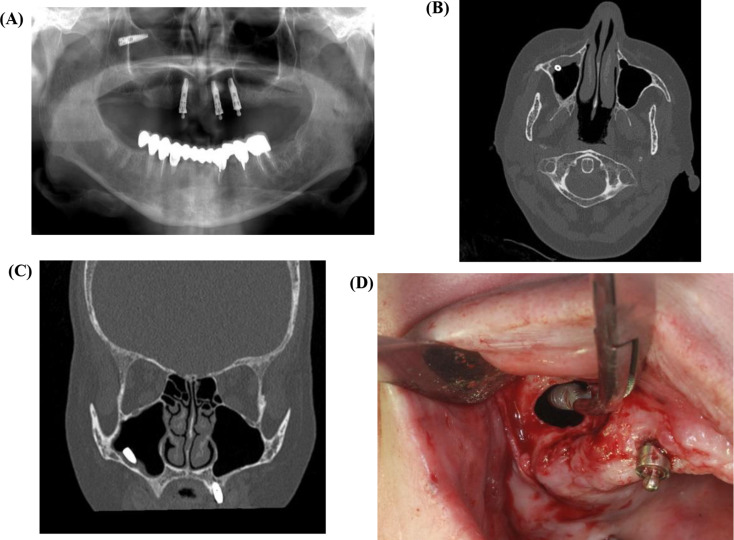

Purpose: This study aims to investigate the potential complication of implant displacement into the maxillary sinus, exploring its etiology and various management strategies, while proposing a systematic approach for clinicians to effectively address this evolving complication.

Materials and methods: This retrospective multi-center cohort study evaluated patients with dental implant migration into the maxillary sinus treated between 2010 and 2023 at two Israeli medical centers. Data included demographics, symptoms, clinical findings, and treatment modalities.

Results: 32 patients (mean age: 62.3 years) were analyzed, with a notable incidence of sinusitis and oroantral fistulas. 91% required surgical intervention, predominantly Functional Endoscopic Sinus Surgery (63%). The majority of displacements occurred during the implantation process, often correlating with clinical symptoms.

Conclusion: As shown in our study, displacement of implants into maxillary sinus, often leads to sinusitis and oroantral fistula. A proposed treatment algorithm emphasizes surgical intervention, particularly Functional Endoscopic Sinus Surgery, based on symptoms and clinical signs.